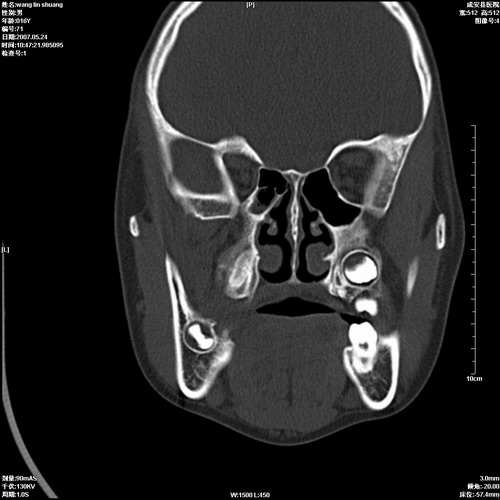

病人,男 16岁,鼻旁右肿胀,其余无不适感,ct图片

典型的右侧上颌骨含牙囊肿,双侧上颌窦、右侧蝶窦炎症。

1、左侧含牙囊肿。

2、双侧上颌窦、筛窦、蝶窦炎;

右侧上颌骨含牙囊肿,全组鼻窦炎